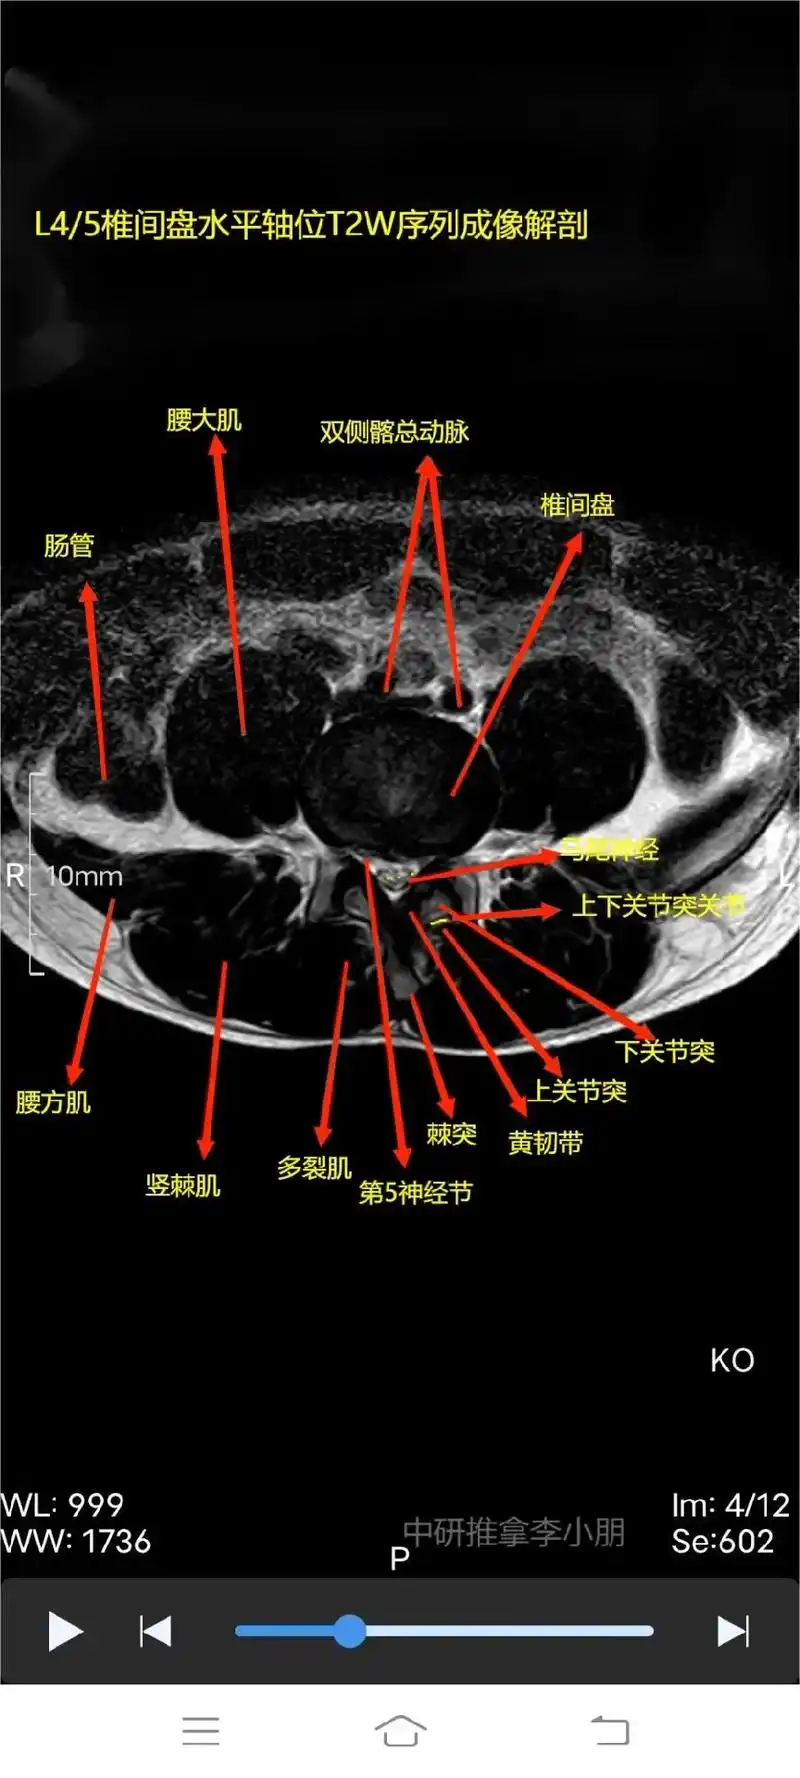

感谢大家的帮助,试着做了三张腰椎核磁解剖,有错误的地方还望大 - 抖